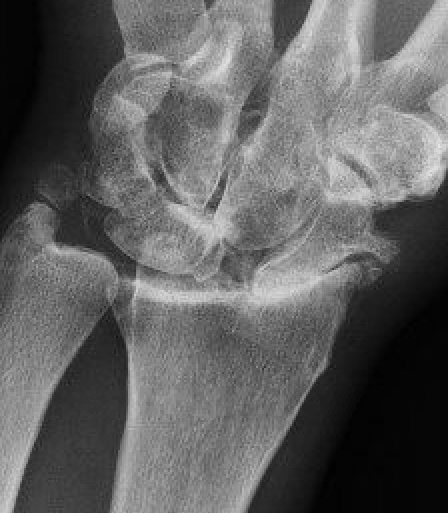

Kienbock's disease